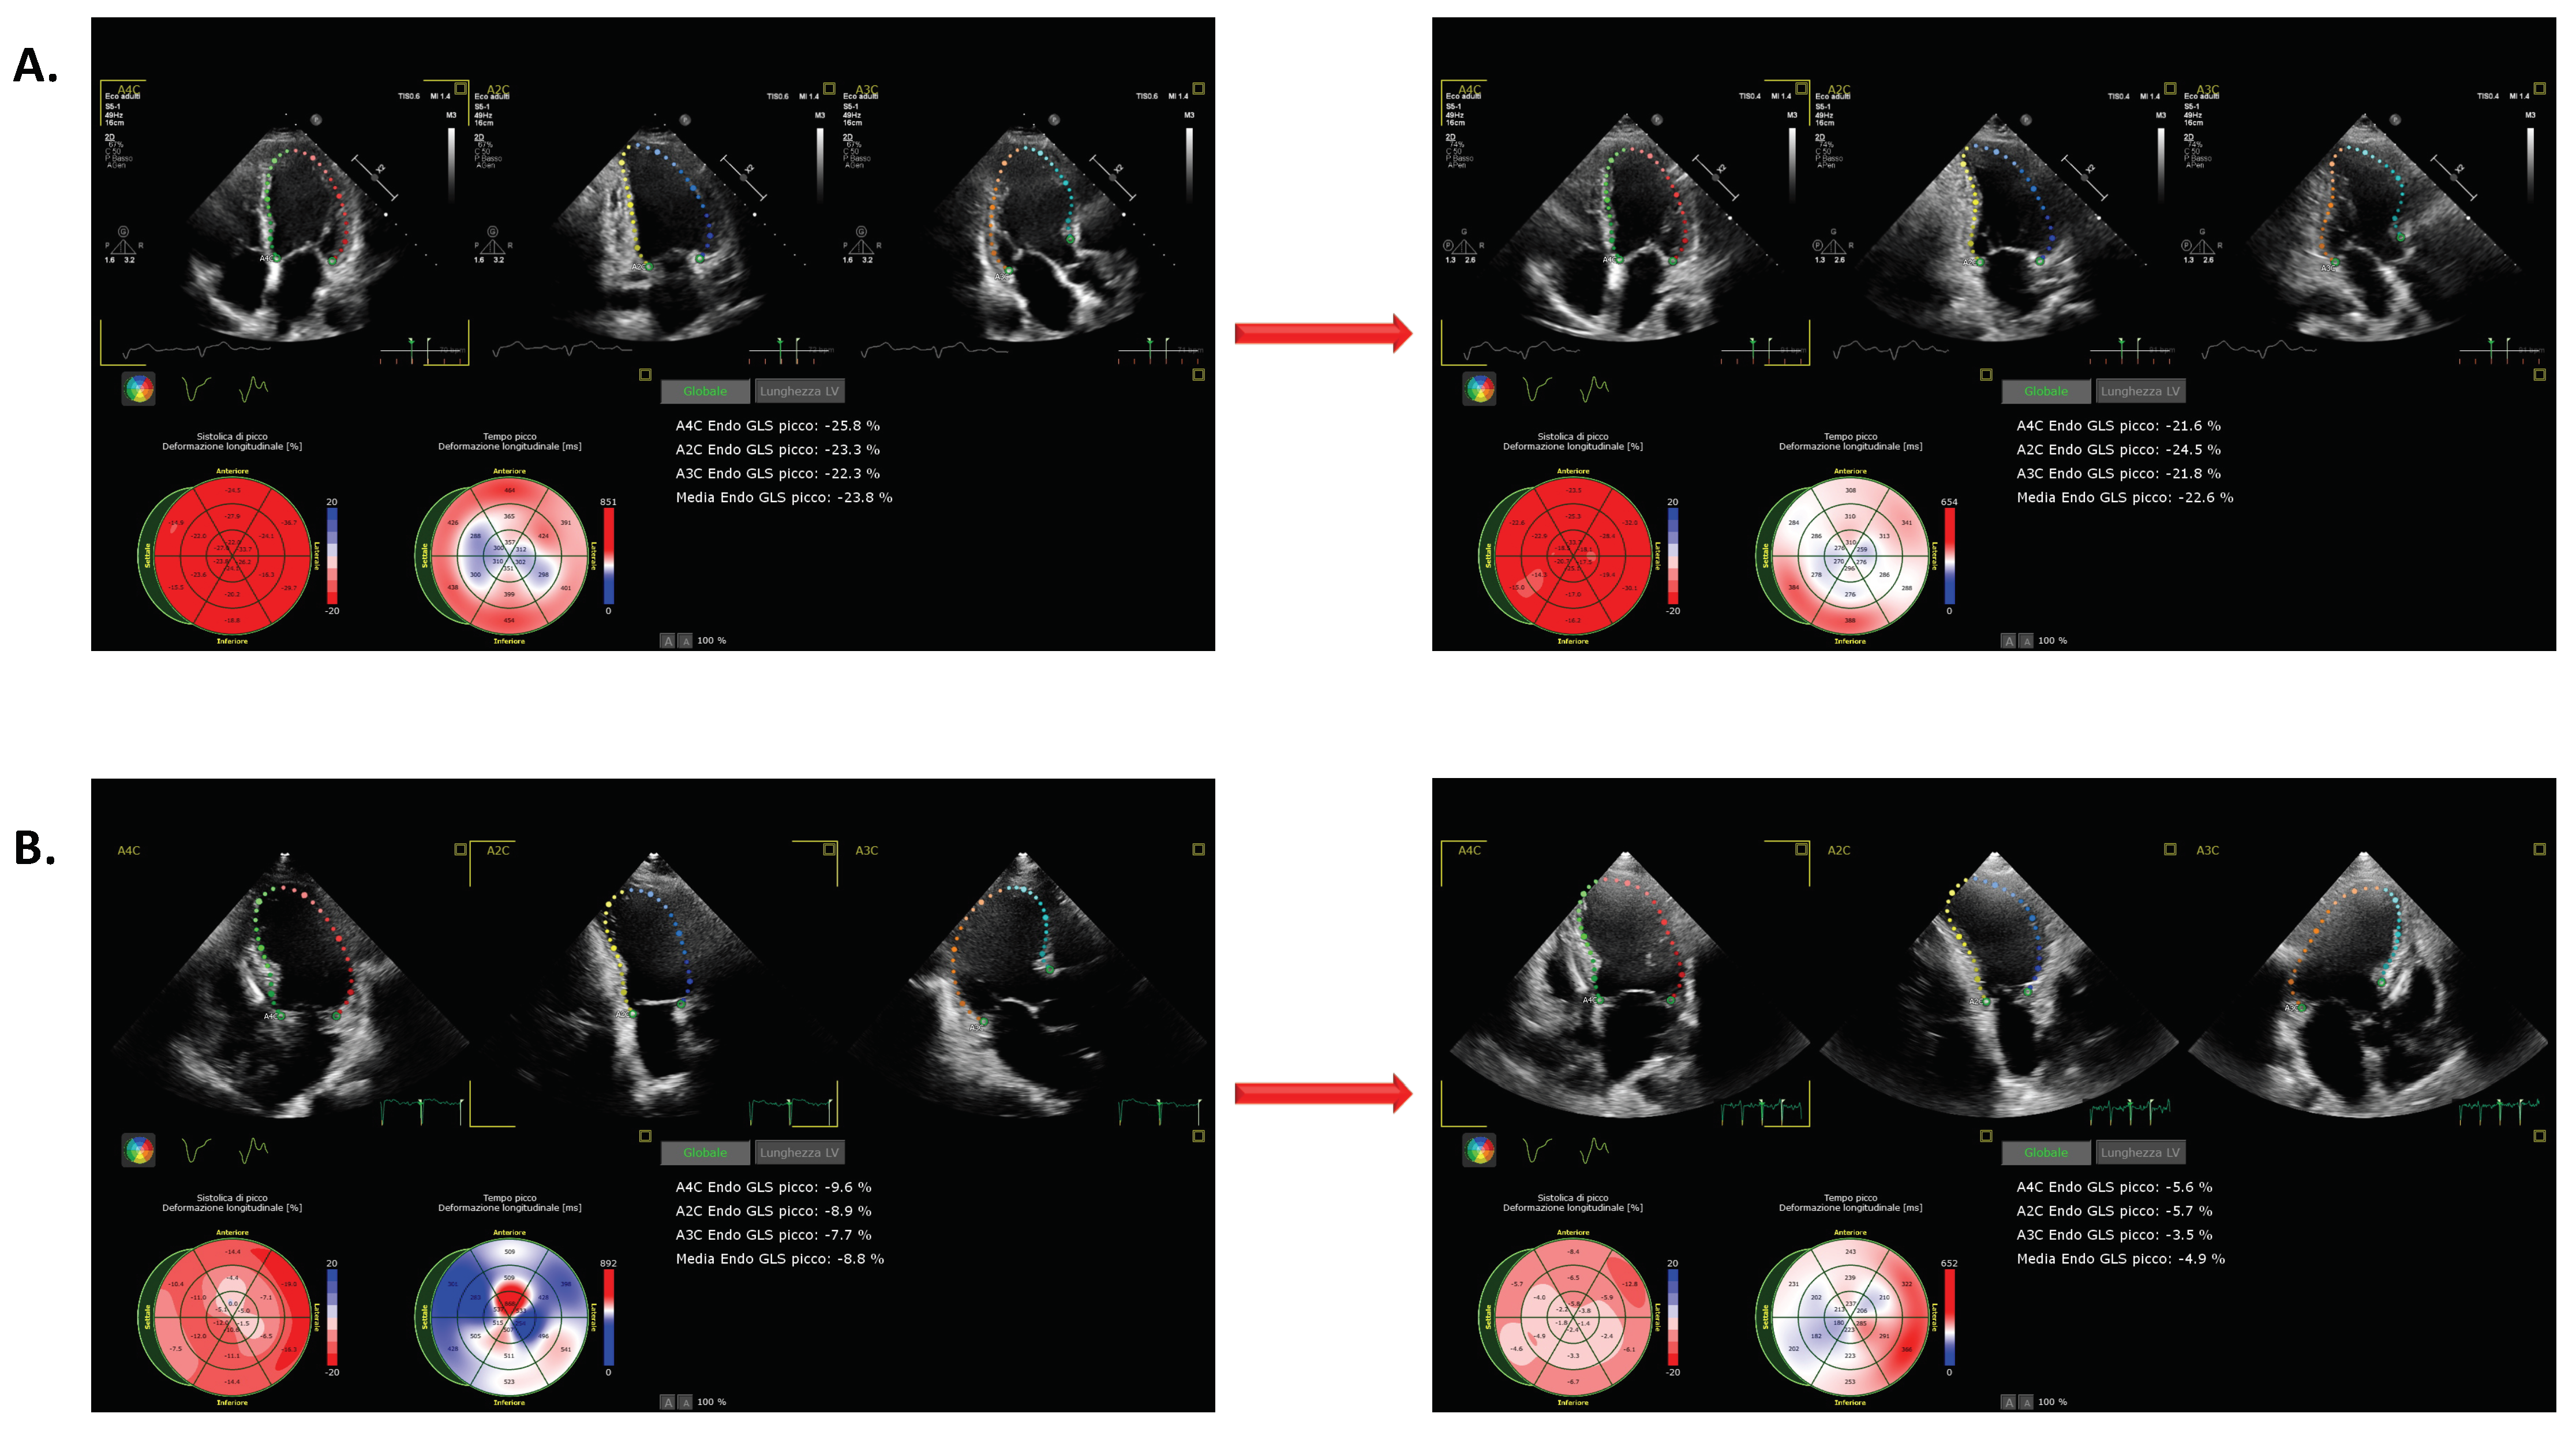

3.3. Changes in LVGLS during Pacing